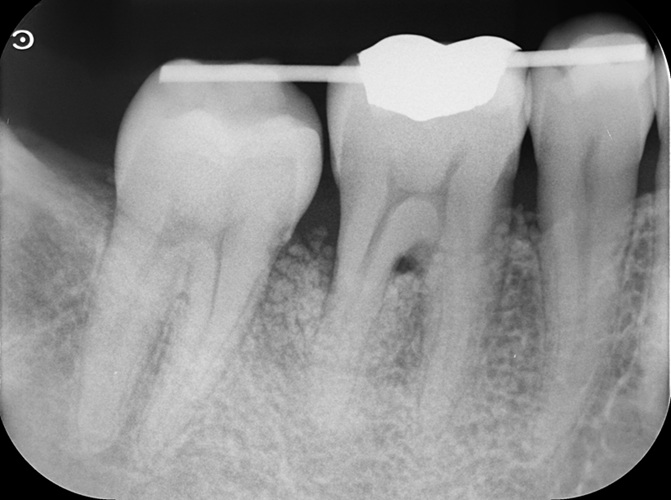

Case2

術前

術中

術後

| 治療説明 | 右下6に重度の歯周病があり、通常の歯周治療でも改善しませんでした。歯周組織再生療法を行い、吸収してしまった骨を再生し、今後の歯周病の進行リスクを減らす事ができました。歯肉退縮もあったため同時に結合組織を移植し、骨と歯肉の再生を同時に行っています。 |

| 治療回数・期間 | 6ヶ月 |

| 副作用とリスク | 手術後に出血、腫脹、疼痛が生じることがあります。手術後は術部の創傷安定のためにブラッシング制限、食事制限があります。手術が複数回となることがあります。 |

| 料金(税込) | 再生療法:165,000円 結合組織移植:55,000円 総額:220,000円 |